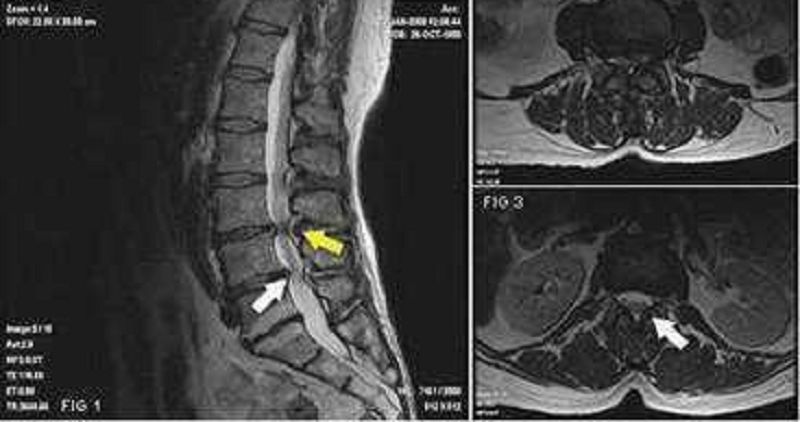

Welche Erkrankung beschreibt dieses Bild?

Spondylolisthese bei Spondylolyse